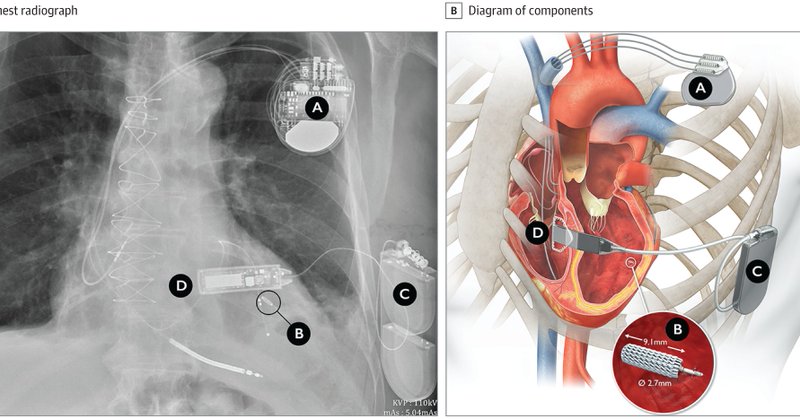

Leadless Ultrasound-Based Cardiac Resynchronization System in Heart Failure https://t.co/y0u3mQOO5R Proud the SOLVE-CRT trial with @JagSinghMD His author interview here:

Interview with Jagmeet P. Singh, MD, DPhil, author of Leadless Ultrasound-Based Cardiac Resynchronization System in Heart Failure. Hosted by Kristen K. Patton, MD.

Leadless Ultrasound-Based Cardiac Resynchronization System in Heart Failure https://t.co/j9kCw8d2Qx

This study assesses the safety and efficacy of a novel, leadless, left ventricular endocardial pacing system for patients at high risk for a cardiac resynchronization therapy upgrade or whose...

📌 Leadless LV ultrasound-based CRT system 👉 Efficacy 👉 Safety #HeartFailure #CRT #CardioTwitter @JagSinghMD @PrashSanders @SeguraCardio @gautamsand @DrJasonAndrade @GiuseppeGalati_ @DhirajGuptaBHRS @ValleAlfonso @AndrewJSauer @HFpEF @DrRajivsankar @drrakeshg1 @DrMarthaGulati